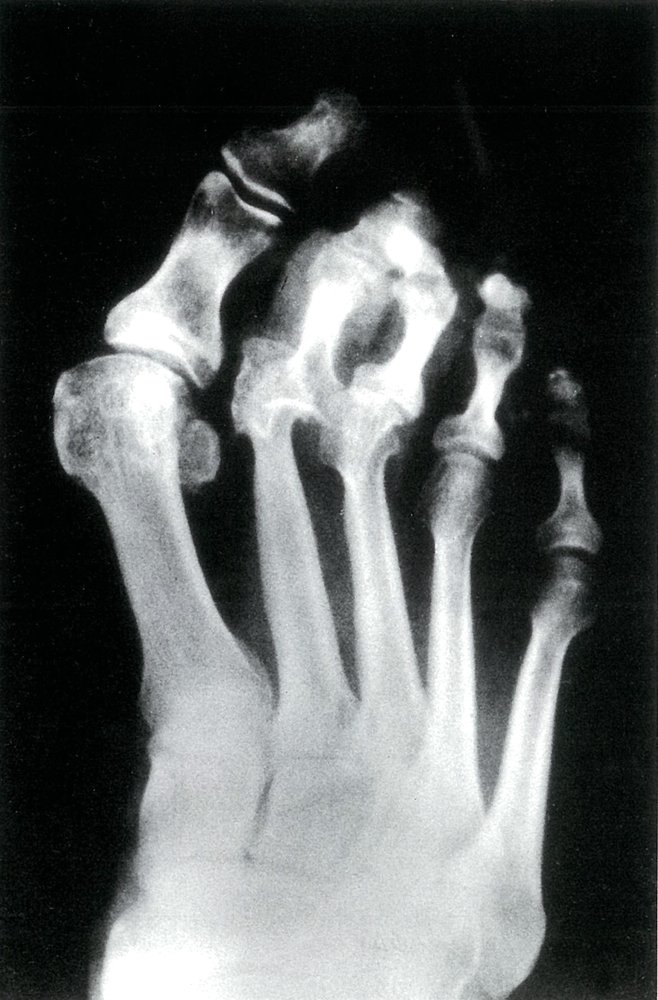

Diabetic neuropathic arthropathy (Charcot foot) [14]

• Neuropathic arthropathy is the development of bone destruction, subluxation/dislocation, and deformity secondary to neuropathy (most commonly diabetic neuropathy).

• The tarsus and tarsometatarsal joints are most commonly affected.

• Clinical presentation depends on the stage.

• Acute stage

• Swelling, warmth, erythema

• Pain is typically mild-to-moderate, as the underlying peripheral neuropathy reduces sensation.

• Chronic stage: painless bony deformities, midfoot collapse (rocker-bottom foot deformity), osteolysis, fractures

• Diagnosis requires x-ray (first line) and MRI (in diagnostic uncertainty).

• Initial treatment is conservative (mechanical offloading, treatment of diabetes); surgery is used for severe or refractory cases.